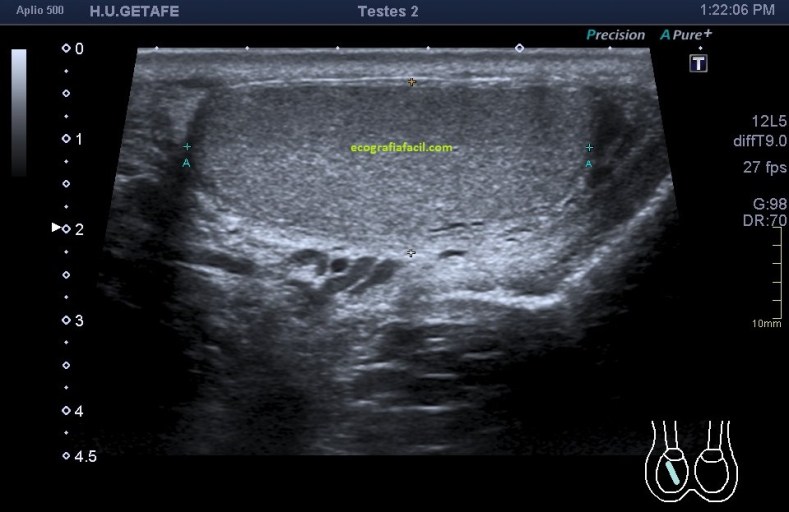

La imagen final demuestra una visión panorámica de los rectos abdominales inferiores demostrando los hallazgos que te he ido explicando durante el post. En este caso me hizo falta utilizar una función del ecógrafo muy útil que es la “función dual”, donde he dividido a pantalla en dos y he podido comparar en una misma imagen tanto a normalidad como la zona patológica, con un considerable aumento de la resolución de la imagen y un aumento en la calidad global de esta tanto en corte transverso como en longitudinal. Esta función dual permite el estudio comparativo con doppler. Muy útil, aunque el almacenamiento masivo de imagen en el pacs hace que esta función haya caído paulatinamente en desuso.